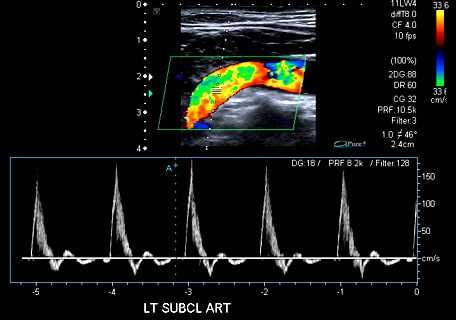

Во время процедуры врач-УЗИ будет исследовать зону от последнего грудного позвонка до крестца. Стандартное УЗИ не дает возможности оценить состояние сосудов в полном объеме, поэтому для диагностики аорты применяется допплерография. В её основе которой лежит возможность отражения волн ультразвука от предметов, находящихся в движении.

Во время допплерографии ветви аорты и она сама окрашиваются в разные цвета, что помогает специалисту УЗИ сделать заключение о состоянии кровотока.

Возможности ультразвуковых приборов позволяют не только оценить размеры, форму и структуру стенки сосуда, но и исследовать характеристики кровотока. Это достигается с помощью доплерографии и цветного допплеровского картирования. Доплерография основана на регистрации ультразвукового сигнала от движущихся эритроцитов и изменении скорости этого сигнала в зависимости от приближения или удаления этих частиц к датчику. Скорость кровотока, определяемого доплерографией, является показателем проходимости сосудов ниже места исследования или в местах сужения сосуда. В суженых местах она значительно усилена; если же существует препятствие для оттока крови ниже места исследования, то скорость снижается.